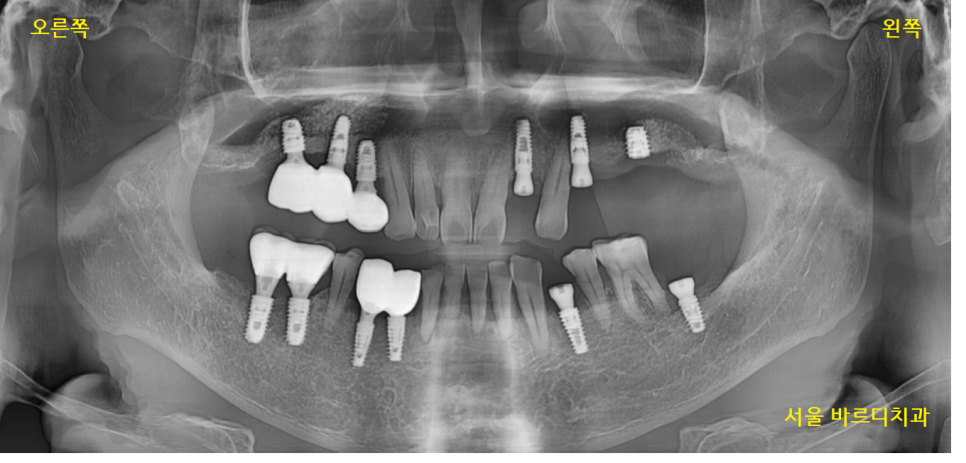

23.09.06

식사를 못하시고 계셔서

오른쪽 먼저 완성 후

한쪽이라도 식사를 하실 수 있게 해드렸습니다.

이때도 디지털 임플란트 기술을 적극적으로

활용했는데요.

스캔 장비를 사용하여

구강 상태를 그대로 재현

보철을 제작해 드렸습니다.